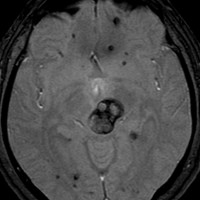

この様な無数の海綿状血管腫を見ることがあります。多くの場合は家族性(遺伝性)の海綿状血管腫です。200個を超える海綿状血管腫があっても普通に何の障害もなく暮らしている患者さんもいます。脊髄の中にも発生しますから,脊髄のMRIもしていただきましょう。

小さな多発性の海綿状血管腫は,T2*(ティーツースター)という左の画像では見えるのですが,右にあるような普通のT1強調画像というのでははっきりみえません。